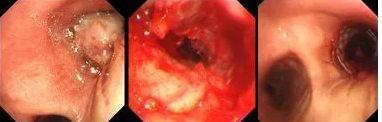

原來,秦爺爺入院時(shí)診斷為“右主支氣管”鱗狀細(xì)胞癌伴壞死。他的右主支氣管被腫瘤完全堵塞,混合性狹窄。面罩吸氧10升/分的狀況下,指脈氧只有85%,無法平躺,呼吸困難,病情十分危急,隨時(shí)有生命危險(xiǎn)。

經(jīng)評(píng)估并與家屬溝通同意后,歐陽海峰副院長決定為患者實(shí)施TTS氣道支架手術(shù)。手術(shù)當(dāng)天,在麻醉手術(shù)中心的配合下,歐陽海峰副院長為患者在局麻下快速凍切腫瘤組織,實(shí)現(xiàn)右主支氣管再通,并經(jīng)氣管鏡活檢孔道迅速植入14*30 TTS支架一枚。支架植入過程耗時(shí)僅6秒,迅速緩解了患者的氣短瀕死癥狀。